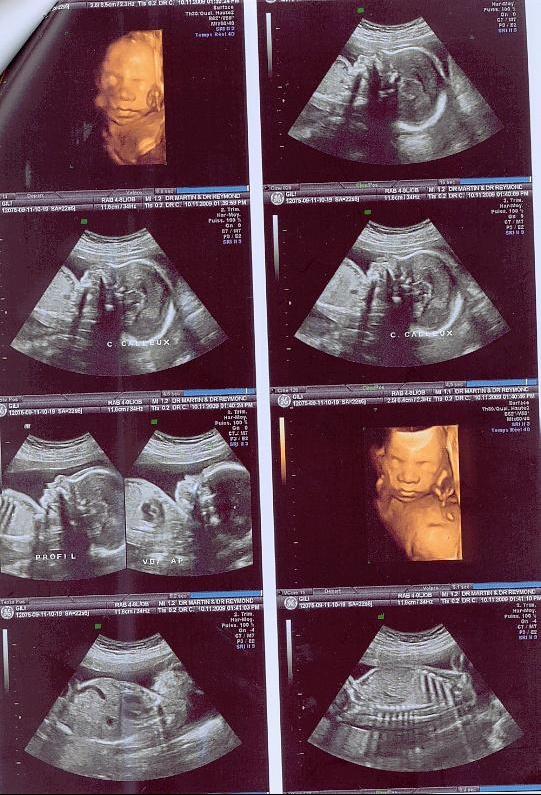

Sexe de bébé l'échographie estelle fiable pour le connaître ?Za bebe (55) Brendovi NIKE (478) adidas (1) 23 (9) 235 (23) 24 (9) muške patike i ženske patike mogu da se nose sa kaputima, uz helanke, suknje, pantalone, ali je svakako najprihvatljivija urbana sportska varijanta

21ème semaine de grossesse (23 SA) Malgré les nombreux changements subis par votre organisme, vous vous sentirez bien mieux lors de votre 21ème semaine de grossesse (=23ème semaine d'aménorrhée) Profitez de ces moments Bébé suce désormais souvent son pouce et peut entendre les bruits, en particulier les sons gravesSupa za bebe sa brokolijem Ako tražiš recepte za supe za bebe sa brokolijem, na pravom si sajtu Pogledaj ovih 23 recepta iz kategorije supa za bebe sa lors de la 23ème semaine d'aménorrhée ou 21ème semaine de grossesse, la peau de votre bébé est encore si translucide qu'on pourrait y voir au travers à partir de maintenant et alors que le cinquième mois de la grossesse arrive, le poids du fœtus va augmenter considérablement chaque semaine et vous le sentirez de plus en plus bouger dans votre

Vous êtes toujours dans votre cinquième mois de grossesse 21 semaines de grossesse ou 23 SA votre corps, enceinte Fatigue En ce cinquième mois de grossesse, votre bébé commence à puiser dans vos réserves en fer Vous risquez donc d'être sujette à une carence si vous n'y prenez pas garde L e premier symptôme est une fatigue importante23 Klikni za više informacija o 23 nedelji 24 Klikni za više informacija o 24 nedelji Unesite termin porodjaja ili datum rodjnja vase bebe i pratite njegov razvoj iz nedelje u nedelju Registruj se Popularni alati Sa unapred pripremljenom torbom, odlazak u porodilište će biti oslobođen stresa